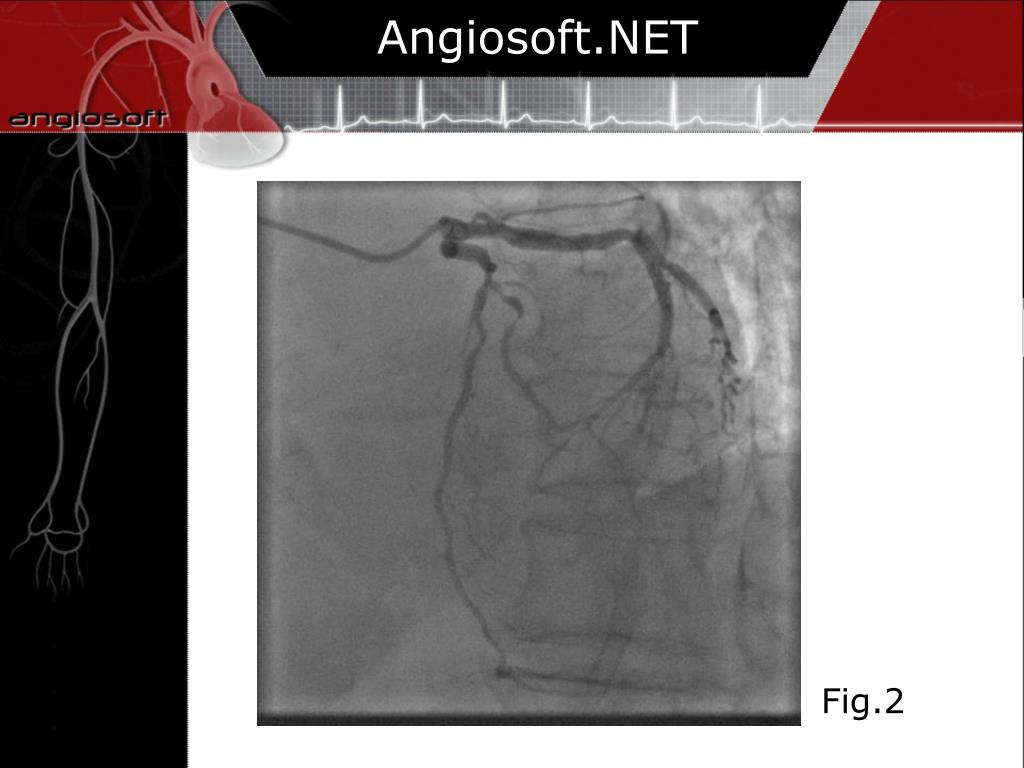

2. Angiosoft.NET • 71 years old woman with recent onset angina and T wave changes in V4-V6 leads. No troponin I elevation. • Procedure: right transradial approach with long Terumo Hydrophilic sheath. • Selective angiography with standard Judkins catheters show disease of LAD-D1 with bifurcation lesion (Fig. 1,2)

4. Angiosoft.NET Fig.2